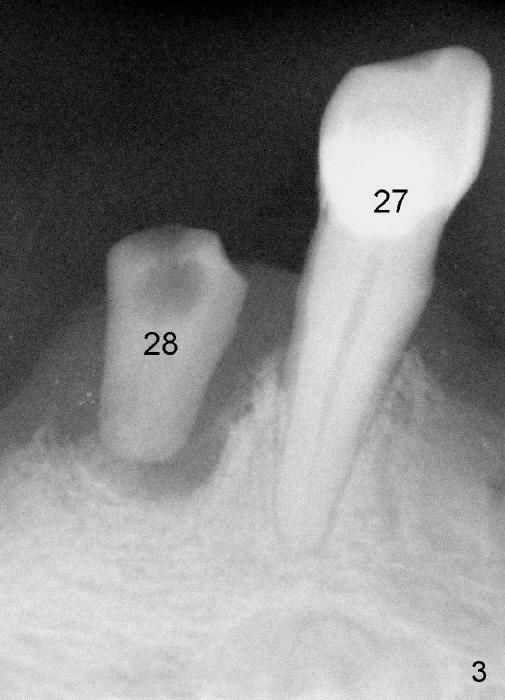

A 73-year-old lady has an existing upper complete denture and a lower flipper. A few days after #23 exfoliation, a 3.5x17 mm one piece implant is placed (Fig.1) and an immediate provisional is fabricated. Later the lower flipper is remade. The one piece implant and the provisional have been doing well for 7 months by the time Fig.2 is taken.

Two provisionals #22 and 28 are dislodged several time while the implants #23 and 28 are healing, 9 and 2.5 months postop, respectively.